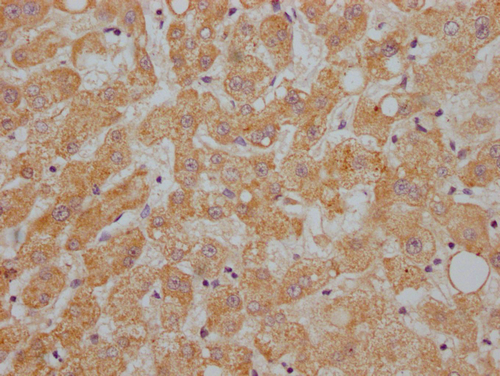

IHC image of CSB-PA001930NA01HU diluted at 1:200 and staining in paraffin-embedded human liver cancer performed on a Leica BondTM system. After dewaxing and hydration, antigen retrieval was mediated by high pressure in a citrate buffer (pH 6.0). Section was blocked with 10% normal goat serum 30min at RT. Then primary antibody (1% BSA) was incubated at 4°C overnight. The primary is detected by a Goat anti-rabbit IgG labeled by HRP and visualized using 0.05% DAB.